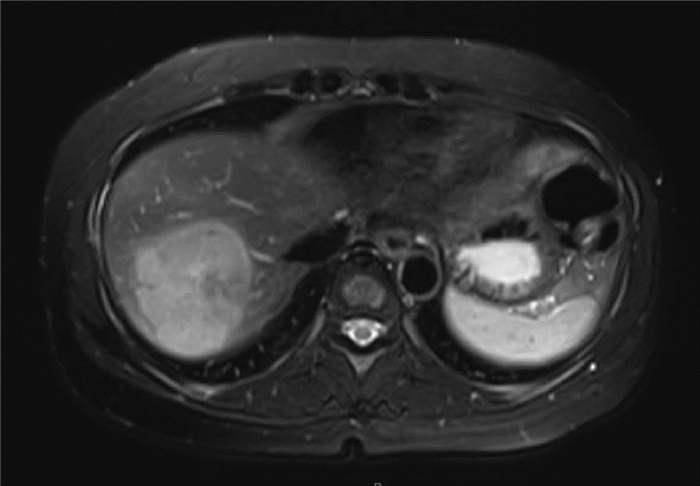

IgG4-related autoimmune hepatitis with subacute liver failure as the initial manifestation: A case report

Li JIANG, Huimin LIU, Qing MAO

2022, 38(1): 170-173. DOI: 10.3969/j.issn.1001-5256.2022.01.028

Abstract(1589) HTML (432) PDF (3941KB)(87)

Abstract: